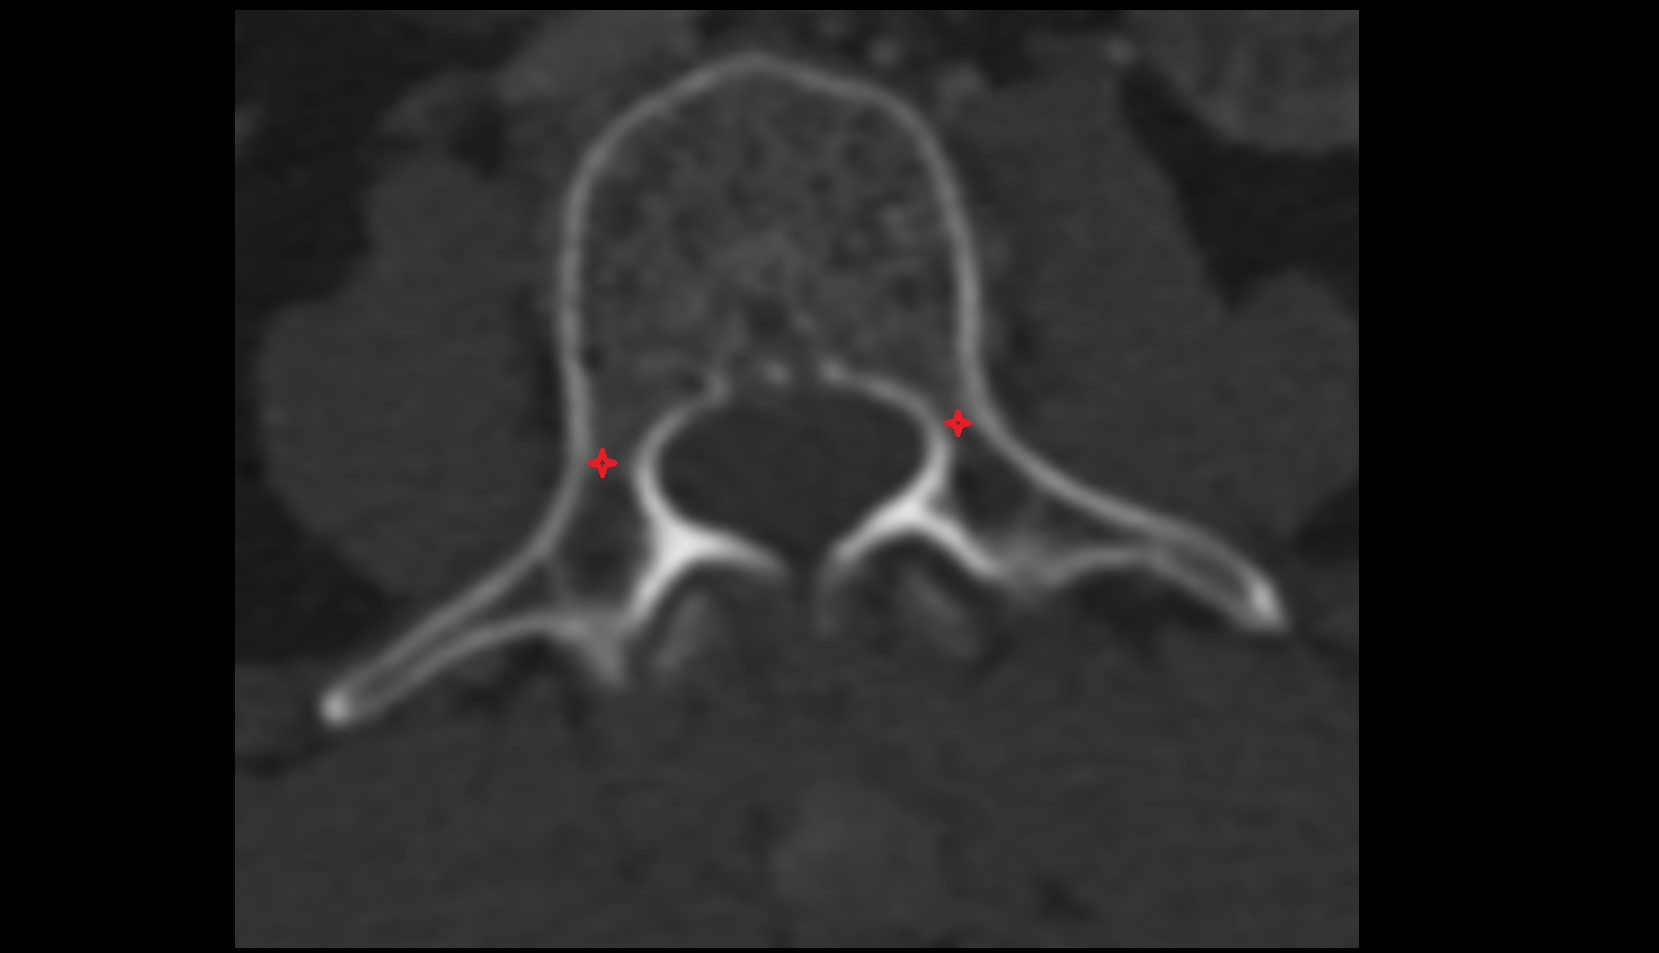

- Annulus fibrosus of intervertebral disc

- Fetal forearm

- Fetal small bowel

- Fetal hand

- Deep femoral vein (profunda femoris vein)

- Femoral shaft